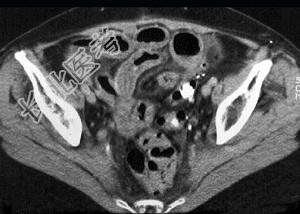

- 单项选择题女,54岁, 直肠癌放疗后一月,阵发性腹痛腹胀, 呕吐应,CT表现如图, 应诊断为 ( )

D、放射性小肠炎